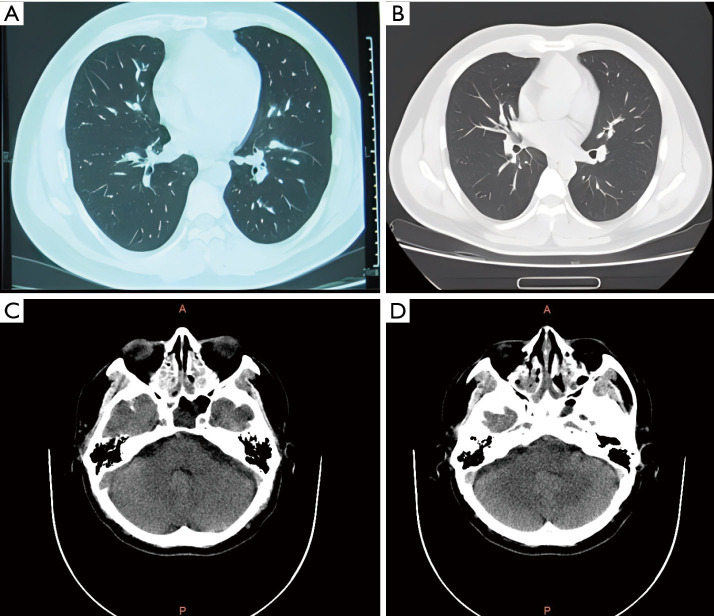

Case description: The patient was initially diagnosed with allergic rhinitis in 2006 and developed cough and wheezing in 2016. In 2017, EGPA was diagnosed based on ACR criteria, with a cumulative score of 14 according to the 2022 ACR and the European League Against Rheumatism (ACR/EULAR) criteria, indicating small and medium vessel vasculitis. The patient showed myocardial, gastric, and neurological involvement, reflecting generalized EGPA. Prognostic assessments should use the five-factor score (FFS), which indicates a 46% 5-year mortality rate for those with an FFS of 2 or higher. This patient had an FFS of 3, tested negative for ANCA, and cardiac emission computed tomography (ECT) confirmed myocardial involvement. However, as EGPA was diagnosed only 13 months after the onset of wheezing, the patient had been undergoing glucocorticoid therapy, as of today (7 years later), has effectively managed the symptoms and facilitated normal daily activities.